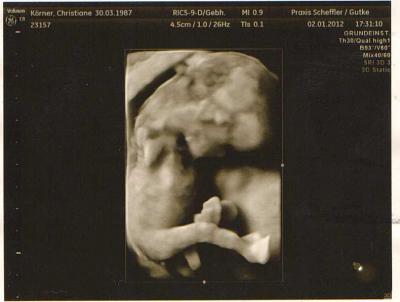

Hallo Ihr Lieben, entschuldigt das ich erst heute schreibe. Ich fühl mich zur Zeit nicht so gut und bin auch krank geschrieben. Habe ständig Kopfschmerzen und deswegen gehe ich auch nicht an den PC im Moment, aber heute morgen geht es noch gut. Ich hatte ja am Montag meinen Arzttermin und es war total schön. Unser Krümelchen hat sich bewegt wie ein Weltmeister und wollte gar nicht ruhig sein. Mein Schatz meinte danach zu mir, so wie sich Krümelchen bewegt, dass müsste ich doch merken, aber ich spüre leider noch nichts. Der Arzt war sehr zufrieden mit dem/der Kleinen und ich wurde eine Woche vorgestuft und hab somit die 12 Wochen rum und bin in der 13. SSW Der E.T. wurde auch knapp eine Woche vorgezogen und der Arzt sagte der bleibt nun auch so stehen. Das Geschlecht werden wir in der 21. SSW erfahren, da meine Termine ja alle schon bis dahin abgesprochen wurden und ich den nächsten Termin bei der Hebamme habe. Der Arzt sagte er schaue immer erst in der 20. SSW weil er dann auch zu 100 % sagen kann was es wird, und hinterher nicht doch noch ein Junge zum Mädchen wird So ist etwas lang geworden. Alle Liebe Euch allen noch Anbei noch eins von meinen fünf Bildern vom Montag

Bild zu Arztbericht vom Montag - Forum für Juli - Mamis